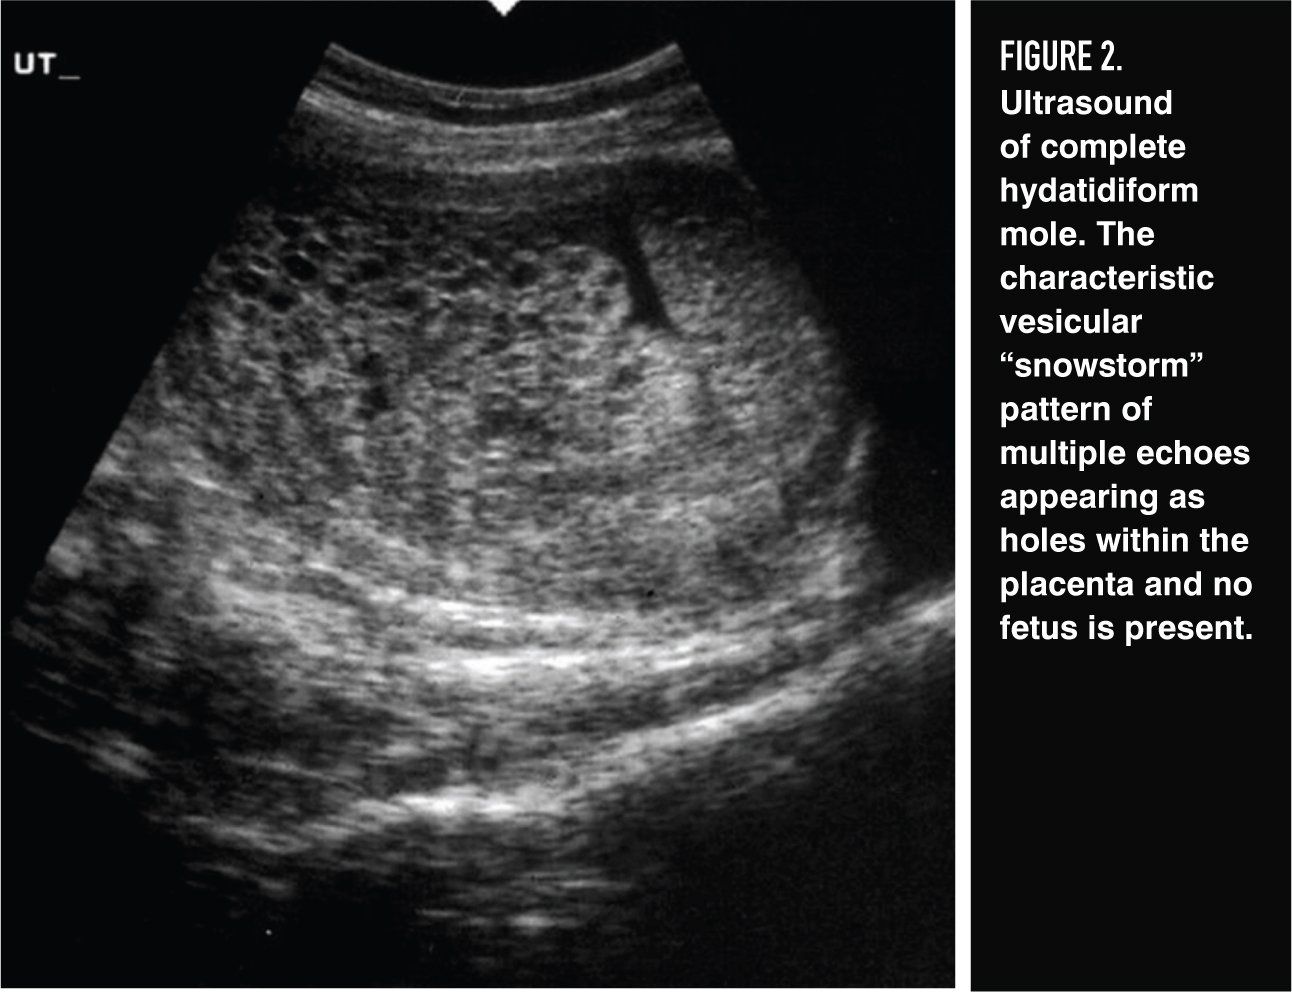

Figure 2

Ultrasonography plays a critical role in the diagnosis of both complete and partial molar pregnancy, and it has virtually replaced all other means of preoperative diagnosis. Because the chorionic villi of complete moles exhibit diffuse hydropic swelling, a characteristic vesicular ultrasonographic pattern can be observed consisting of multiple echoes (holes) within the placental mass and usually no fetus (Figure 2). Ultrasonography may also facilitate early diagnosis of a partial mole by demonstrating focal cystic spaces within the placenta and an increase in the transverse diameter of the gestational sac.12